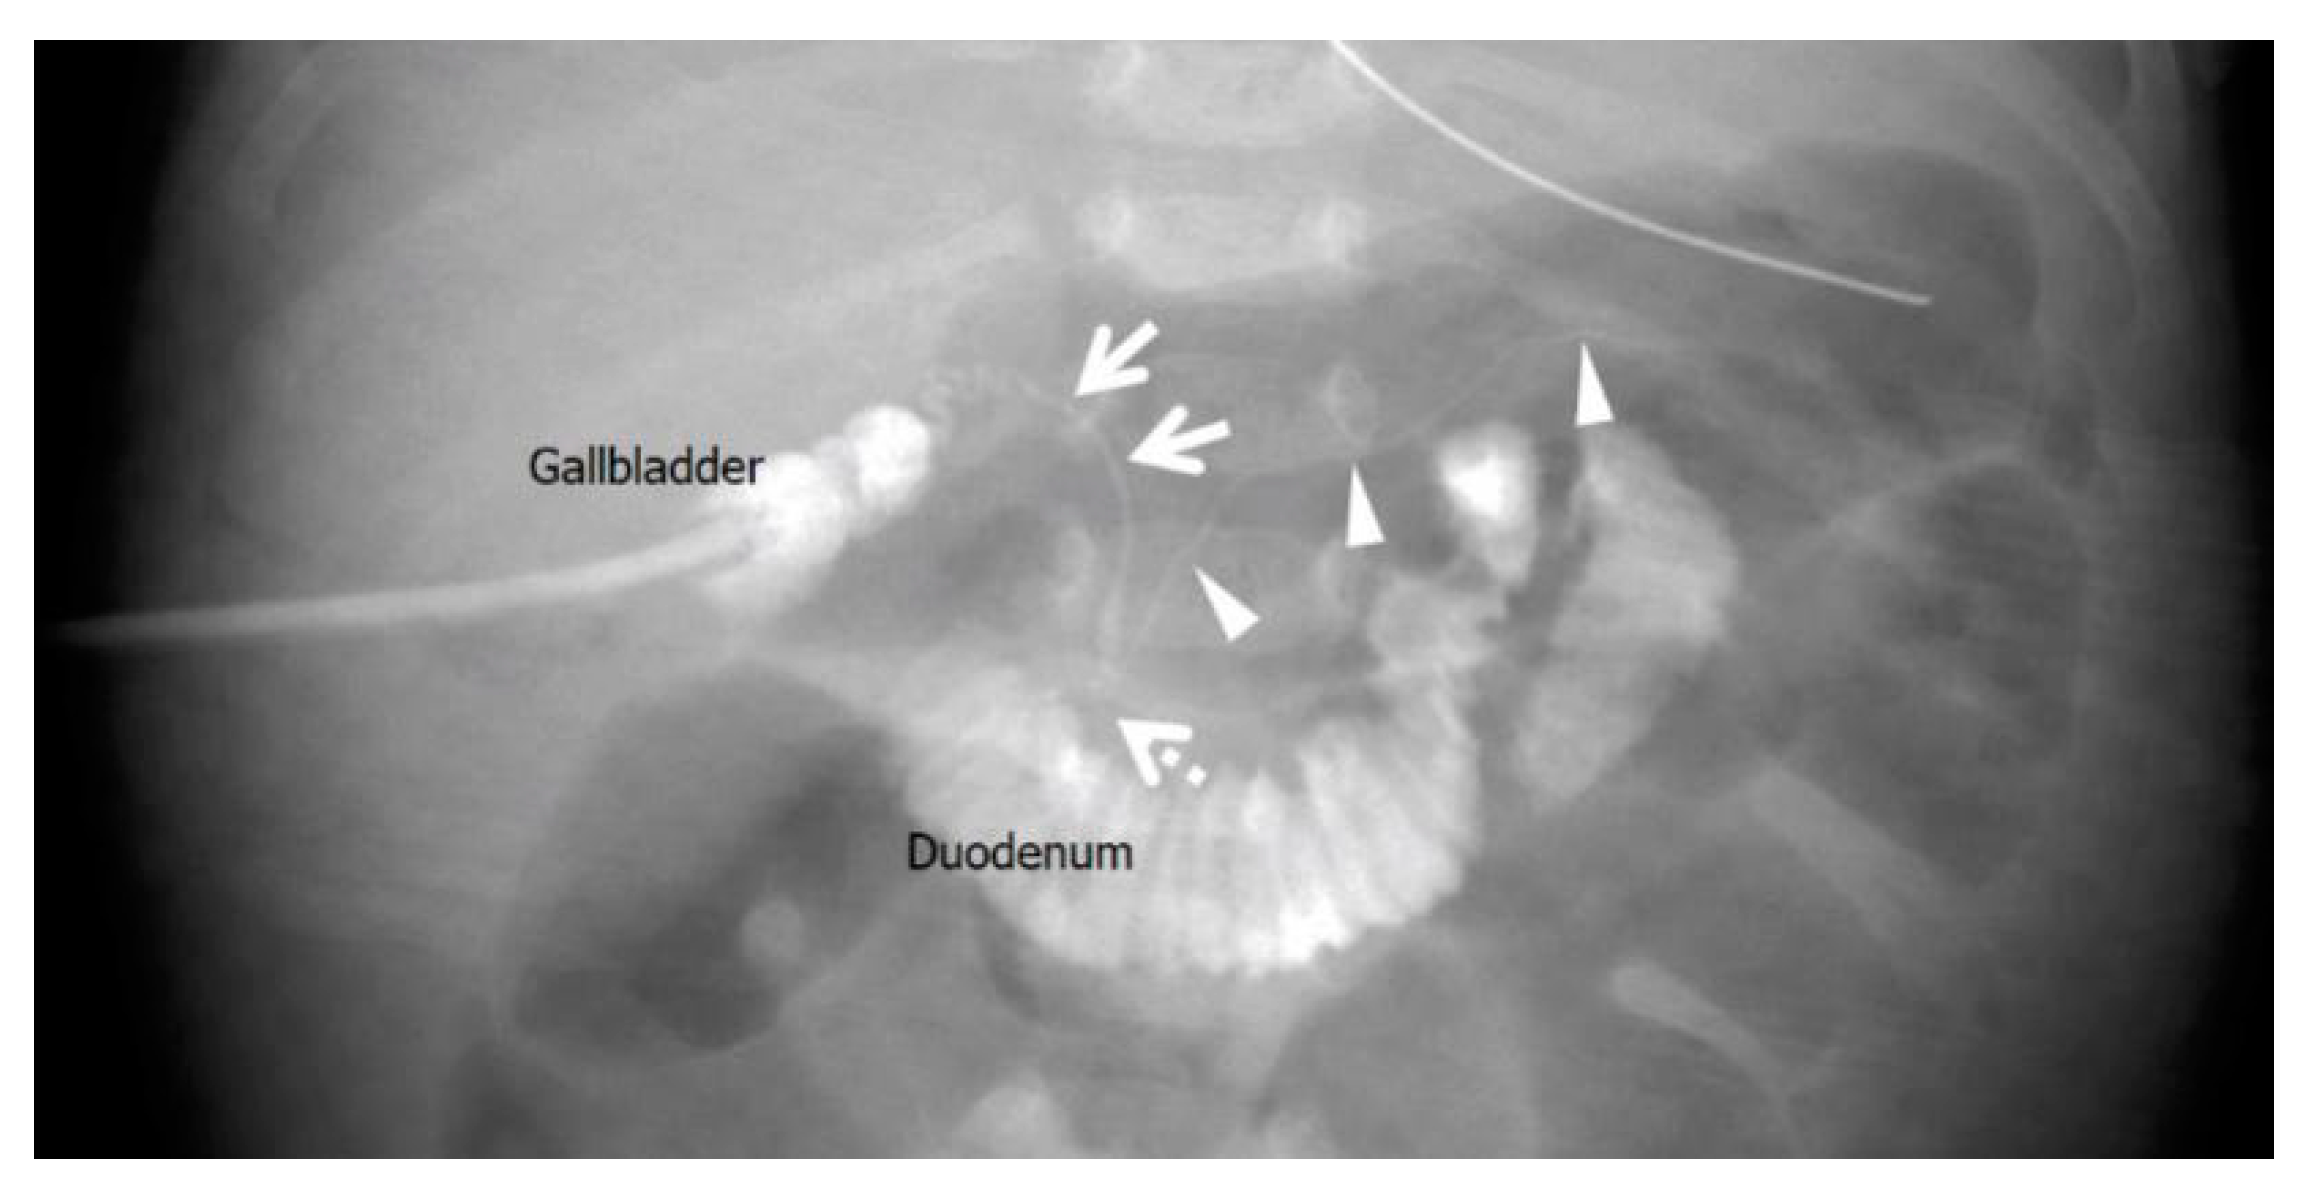

2.2. Case 2: 67-Day-Old Girl